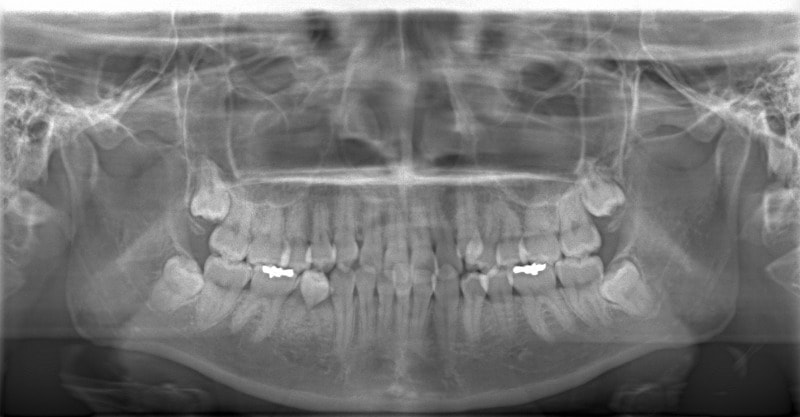

検査時パノラマレントゲン

特に小臼歯部に叢生があり、8番(親知らず)も埋伏しています。8番と7番の接触部分に吸収が若干あるような所見が認められます。

治療中のパノラマレントゲン

歯根吸収もなく、パラレリング(平行性)も確保されております。